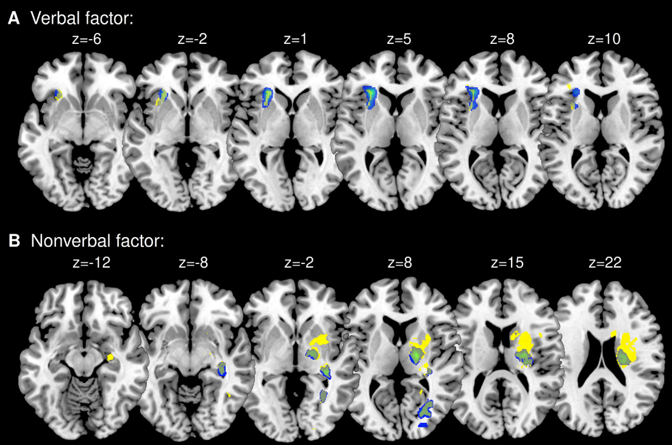

De verdad ¿existen diferencias anatómicas entre tests neuropsicológicos "verbales" vs "no verbales"?

En un impoluto estudio llevado a cabo por Mock et al. (2020) y publicado en la prestigiosa revista Cortex estudian las correlaciones entre las áreas de lesión de 114 sujetos que había sufrido un ictus y su rendimiento en tests de memoria. Los autores incluyen tests de memoria administrados por "canales verbales" ( CVLT, WMS Textos ) vs otros administrados por canales "no verbales" ( VisualDesignLearning 15 dibujos, Test de las rutas, FCREY ) y concluyen que: 1 Existen diferencias neuroanátómicas según el canal sensorial utilizado. 2 Los tests administrados por vía "verbal" se relacionaban más con áreas de lesión en hemisferio izquierdo: ínsula y áreas subcorticales (putamen, corona radiata y cápsula externa). 3 Los tests administrados por vía "no verbal" se relacionaban más con áreas de lesión en hemisferio derecho: lóbulo temporal medial (hipocampo, giro fusiforme, giro temporal inferior), ínsula y giro frontal inferior (par operacularis), occipital (cisura calcarina y giro lingual) y áreas subcorticales (caudado, putamen, globo pálido y tálamo; cápsula interna y externa, corona radiata y fascículo fronto-occipital superior). ¿Cómo acostumbras a evaluar? ¿Utilizas siempre el mismo canal para evaluar el sistema de memoria? Tras la lectura de este artículo ¿qué preguntas te haces?